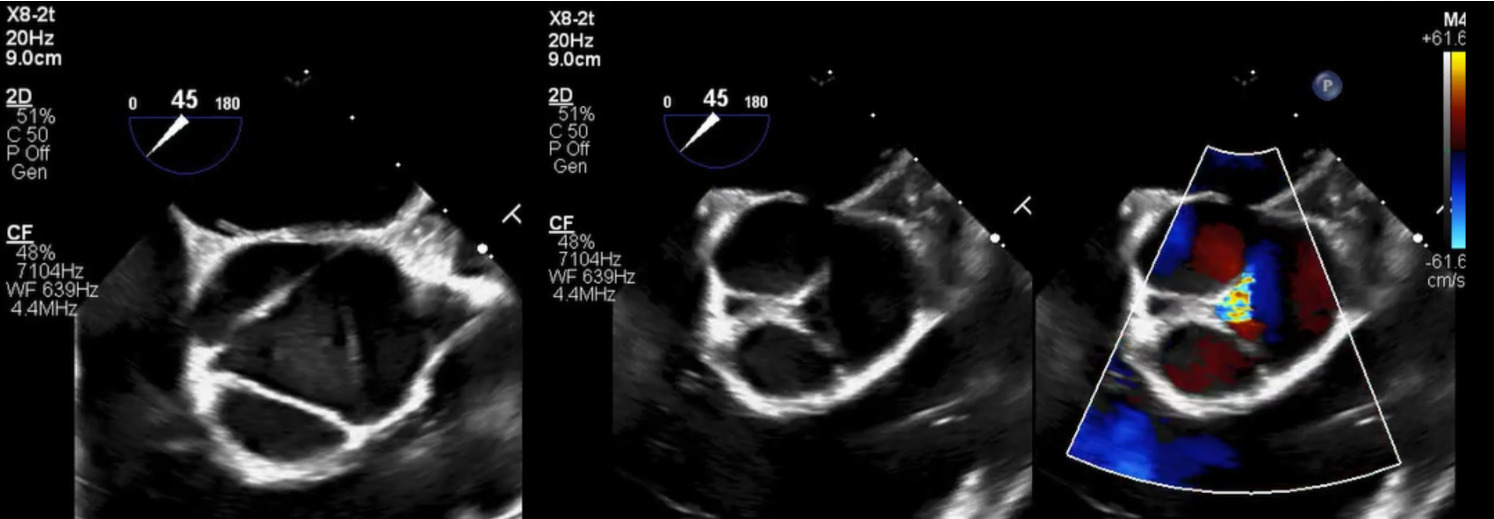

Brain and neck magnetic resonance angiography (MRA) showed no acute or significant vascular abnormality. Transesophageal echocardiogram showed severe aortic regurgitation, trileaflet thickened aortic valve, enlarged ascending aorta 45 mm, normal left ventricular systolic function and patent foramen ovale (Figure 1, Figure 2 and Figure 3). Calculated aorta size index (aortic size cm/body surface area m2) was moderate-severely increased, 2.7 cm2/m2. Mild immobile atherosclerosis of the aorta was noted.

Aortic root pathology showed significant destruction of aortic wall with extensive necrosis and fibrosis (Figure 4).